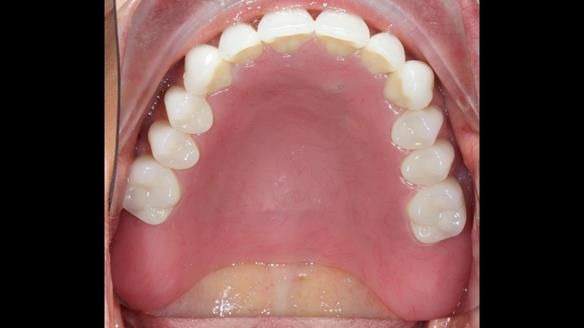

We provided her with an immediate upper denture (Mk 1), followed by a definitive metal-based upper denture (Mk 2). A lower removable partial denture was discussed, to be made only if needed once the upper treatment was complete. However, at review, this wasn’t necessary — Adnana had excellent neuromuscular control and function, even with a shortened dental arch (SDA).

Rowan, Sam Hesketh and Chris Hesketh provided the stunning technical work. I am very lucky to have them.

- Definitive denture (Mk 2), metal-based and custom-designed for her face

- A restored smile, restored lip support, and a patient who owned the journey